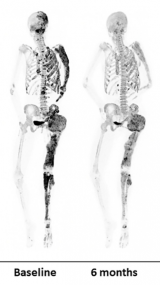

NIH强调PET成像在罕见骨病研究中的作用

在II期临床试验中,研究人员在基线和接受高剂量药物6个月后使用F-18氟化钠(NaF)放射性示踪剂对患者进行PET/CT扫描。Boyce博士指出,虽然成像显示denosumab有希望,但在停止用药后,除1名患者异常骨转换恢复,剩余4名患者的骨转换超过了治疗前的水平。